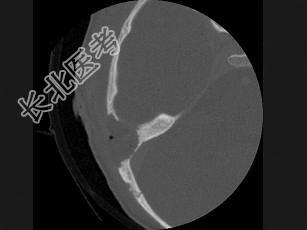

- 单项选择题女性,17岁, 右耳乳突区隐痛,右耳后乳突区出现包块, 逐渐增大,CT检查如图所示, 请选择最可能的 ( )